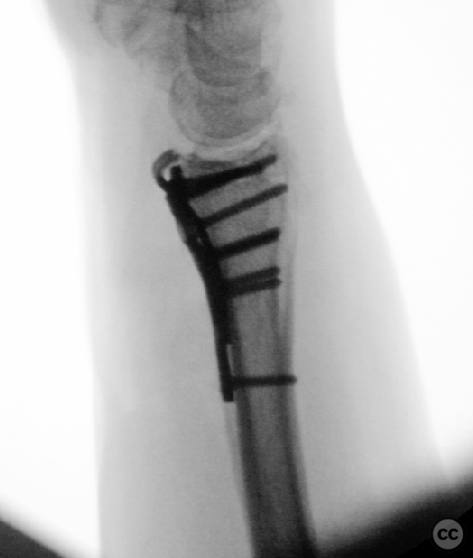

Anatomical surgical approach:  A longitudinal incision was made over the flexor carpi radialis (FCR), zigzagging over the wrist crease. Subcutaneous dissection and incision of the FCR tendon sheath were performed, followed by transection of musculus pronator quadratus fibers along the radial border of the distal FCR. The FCR tendon was retracted ulnarly, and the antebrachial fascia incised. Musculus flexor pollicis longus was identified and retracted ulnarly. The pronator quadratus was incised along its radial border and the watershed line, then elevated subperiosteally to expose the distal radius. Extended distal release of the FCR allowed wide exposure of the ulnar aspect of the lunate facet and volar lip. The flipped volar ulnar fragment was de-rotated and provisionally fixed with a Kirschner wire. Ligamentotaxis for radial styloid reduction was achieved using Kirschner wires in the scaphoid and distal radius, with a wire spreader applied for distraction. Provisional fixation was achieved with multiple Kirschner wires. A mini-fragment T-plate, cut and shaped as a hook plate, was applied to the volar ulnar lip fragment, fixed with bicortical screws, and used to engage dorsal fragments. The radial styloid was addressed with a contoured T-plate, similarly fixed with bicortical locking screws. Final multiplanar fluoroscopy confirmed anatomical reduction and hardware placement.

The flipped volar ulnar articular margin fragment was irreducible by closed means due to capsular attachment and required direct open de-rotation and fixation. The impaction and proximal displacement of the radial styloid fragments were challenging due to persistent traction from musculus brachioradialis and scaphoid pressure; ligamentotaxis using Kirschner wire spreader over the scaphoid facilitated reduction. Fragment-specific fixation was necessary: a custom-shaped hook plate for the volar ulnar lip fragment provided stable fixation and prevented dorsal instability, while a separate T-plate addressed the radial styloid. Bicortical locking screws were used to secure both plates, with some screws engaging dorsal fragments from the volar side. Careful adaptation of pronator quadratus over hardware minimized risk of musculus flexor pollicis longus irritation. Additional suture stabilization of radiocarpal ligaments to pronator quadratus provided secondary ligamnetal support.

Orthopaedic implants used:   - 1.0 mm Kirschner wire (provisional fixation) - 1.8 mm Kirschner wire (scaphoid traction) - 2.0 mm Stryker mini fragment T-plate (cut/shaped as hook plate) - 2.4 mm T-plate (radial styloid fixation)